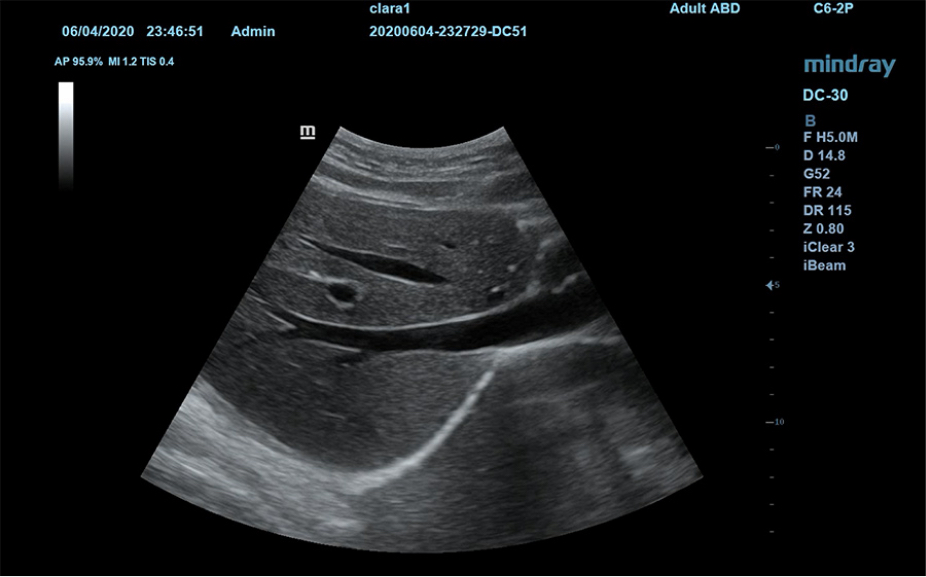

Sistema de diagnĂłstico ecogrĂĄfico

DC- 30

AtenciĂłn primaria con una excelente visiĂłn

FullHD

ImĂĄgenes clĂnicas